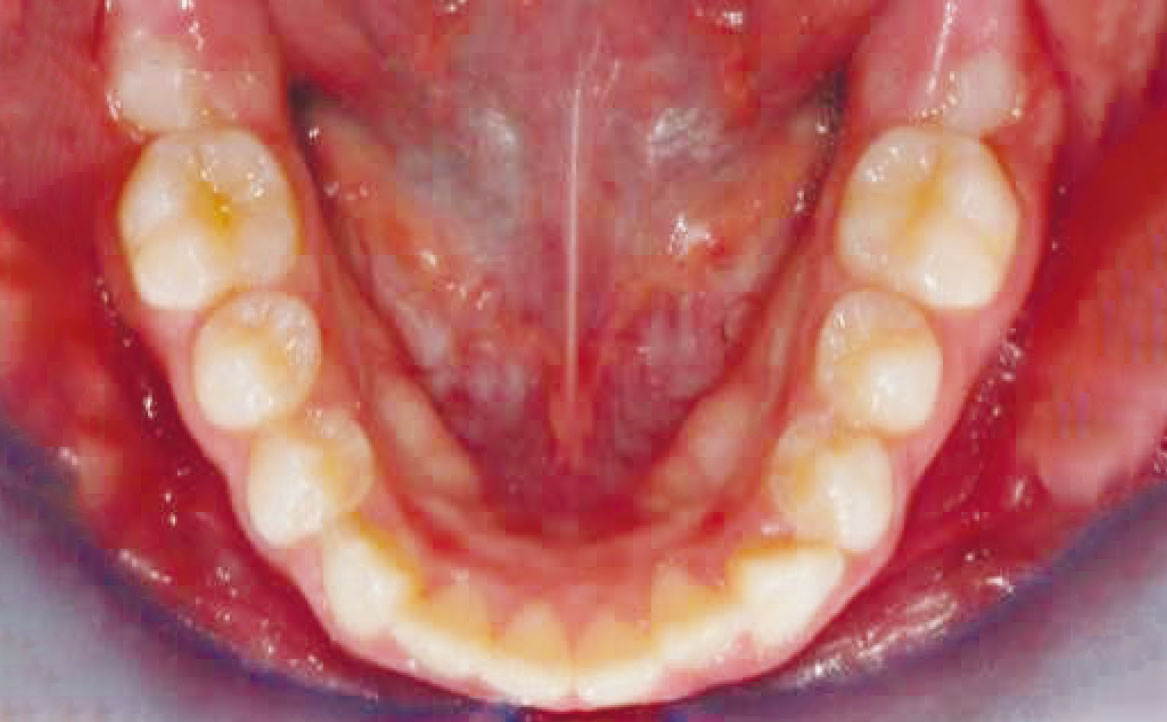

Viene eseguita la consueta raccolta dei records: fotografie intra ed extra orali, modelli e indagini radiografiche di primo livello (OPT e teleradiografia latero-laterale) (fig. 2-11).

L’esame clinico e strumentale consentono di porre diagnosi di malocclusione di classe II di natura scheletrica, associata a retrusione mandibolare. In questa condizione, la mandibola mostra dimensioni e volume inferiori rispetto ai valori medi per età scheletrica e sesso.

Al fine di risolvere la contrazione dell’arcata mascellare sul piano trasverso è stato applicato un disgiuntore rapido ancorandolo ai denti decidui ed estendendo i bracci palatali saldati agli elementi 53 e 63. Mentre, per la risoluzione della carenza mandibolare è stato pianificato l’utilizzo del Twin Block.